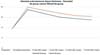

Both groups presented progressive reabsorption. ►Table 1 and ►Fig. 5 show the change in mean subcutaneous thickness in both groups.

In the decanted graft group, the average reduction compared with the initial thickness after lipofilling was 9.90% on day 15, 19.27% on month 1, 23.59% on month 3, and 26.36% on month 6. In the filtered graft group, the average reduction compared to the initial thickness after lipofilling was 7.74% on day 15, 14.85% on month 1, 20.67% on month 3, and 22.80% on month 6 (►Fig. 6). ►Figs 7–8 reveal the ultrasound change in subcutaneous tissue’s thickness before and after lipofilling. ►Figs. 9–10 show the pre-and postoperative results of one patient from each group.

The comparison of subcutaneous thickness reduction at 6 months between the graft decantation and filtration techniques showed no statistically significant difference (p ¼ 0.59).